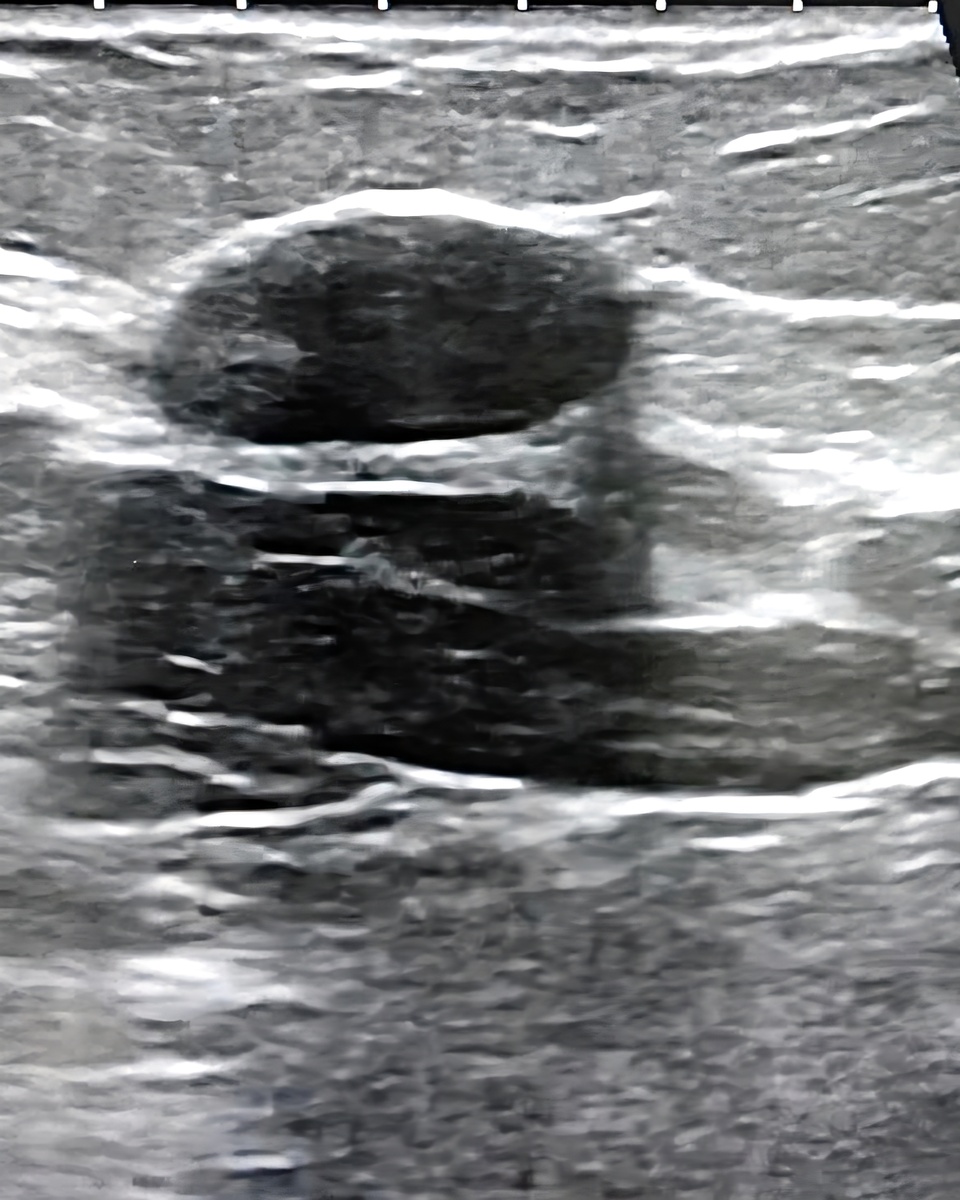

Так выглядит на УЗИ

Даже если УЗИ, маммография или МРТ показывают «типичную» фиброаденому, точный диагноз ставится только после биопсии (забора клеток для анализа).